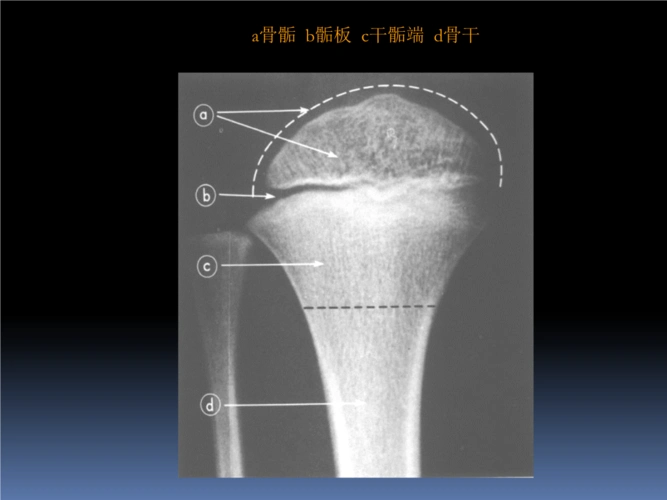

儿童骨骺损伤

儿童的长骨分为四个区域,包括骨骺,骺板(即生长板),干骺端,骨干.